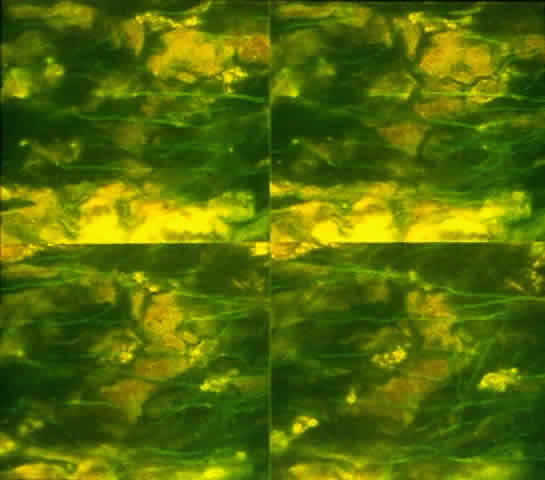

Fig. 15. Immunolocalization of vasoactive intestinal peptide in conjunctival flat mount. Fluorescence micrographs are a montage of sections imaged parallel to the conjunctival surface at 1-μm intervals with a confocal microscope. Vasoactive intestinal peptide-containing nerves appear as green lines.

Fig. 16. Fluorescence micrograph of section from inferior conjunctiva showing tyrosine hydroxylase (TH)-containing nerve fibers. Presence of TH indicates that sympathetic nerve fibers surround individual goblet cells. (Original magnification; × 600. Dartt DA, McCarthy DM, Mercer HJ et al: Localization of nerves adjacent to goblet cells in rat conjunctiva. Curr Eye Res 14:993, 1995)